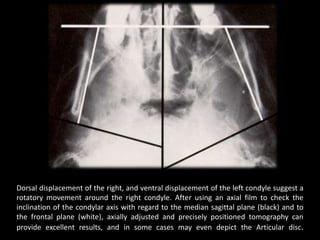

Dorsal displacement of the right, and ventral displacement of the left condyle suggest a

rotatory movement around the right condyle. After using an axial film to check the

inclination of the condylar axis with regard to the median sagittal plane (black) and to

the frontal plane (white), axially adjusted and precisely positioned tomography can

provide excellent results, and in some cases may even depict the Articular disc.